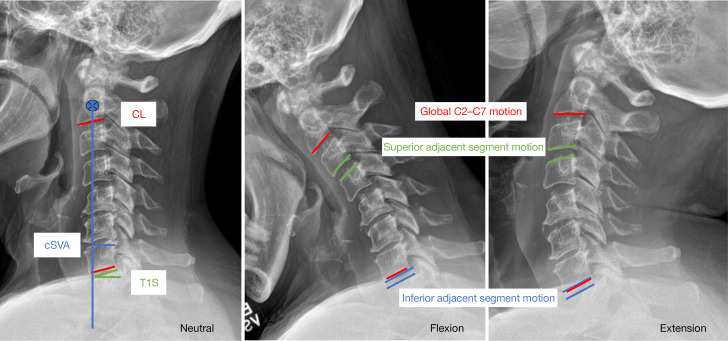

Methods: This is a single-center, multi-surgeon, retrospective cohort study of 2- and 3-level ACH and ACDF cases between 2013 and 2021. Degrees of motion were analyzed on flexion/extension views using Cobb angles to measure global (C2-C7) construct and adjacent segment lordosis. Neutral lateral X-rays were analyzed for alignment parameters, including global lordosis, cervical sagittal vertical axis (cSVA), and T1 slope (T1S). Differences were determined by independent t-test and Fisher's exact test.